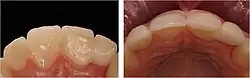

Eine wichtige Voraussetzung für die Versorgung mit Klebebrücken ist die relative Kariesfreiheit der Pfeilerzähne und ein ausreichender Zahnschmelz, der beim Klebevorgang erforderlich ist.[1] Kleinere Füllungen in den Pfeilerzähnen können belassen werden, sollten aber vor dem Kleben des Zahnersatzes speziell behandelt (konditioniert) werden.

Generell können Klebebrücken aus mit Keramik verblendetem Metall zum Ersatz von Front- und Seitenzähnen verwendet werden, während sich der Einsatz von Vollkeramikbrücken auf den Frontzahnbereich beschränken sollte.[1] Wenn Metall als Gerüstmaterial gewählt wird, sind Nichtedelmetalllegierungen (in der Regel aus Kobalt-Chrom) Edelmetalllegierungen vorzuziehen, da Erstere ein höheres Elastizitätsmodul aufweisen und sich besser verkleben lassen.[20]